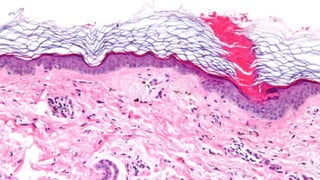

Histopathology of

Porokeratosis

Hereditary disorder of

keratinization characterized by

expanding atrophic anular patch(es)

surrounded by prominent keratotic

ridge called the cornoid lamella